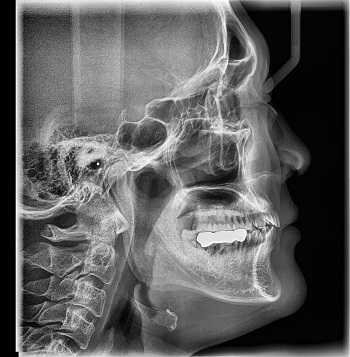

Что покажет рентген

Рентген - это самый широко доступный тип обследования. В Санкт-Петербурге его можно сделать быстро на платной или бесплатной основе как в частных, так и в государственных клиниках и больницах. Основная задача рентгенографии - дать общее представление об изменении структуры органов и костной ткани. С помощью рентген-аппарата врач может хорошо визуализировать:

Основное преимущество рентгенографии заключается в том, что это быстрый и дешевый метод сканирования. Однако по точности и диагностической ценности он безусловно уступает как УЗИ, так и таким высокотехнологичным методам исследования, как МРТ и КТ.

В основе физики работы рентген-аппарата лежат просвечивающие способности рентгеновских лучей. Получение плоского двухмерного изображения основано на ослаблении рентгеновского излучения при его прохождении через различные ткани. При рентген-сканировании пучок излучения, проходя через ткани организма, которые обладают различной плотностью, рассеивается и тормозится. Таким образом, на пленке возникают изображения разной степени интенсивности. Лучевая нагрузка при рентгенографии небольшая, но она всегда есть и может составлять от 0,1 до 1 мЗв. Поэтому рентгенография запрещена для беременных женщин, а здоровому человеку рентген можно делать 1- 2 раза в год.

Кроме дозы облучения у рентгеновского сканирования есть один существенный диагностический недостаток - плоская картинка. Поскольку рентген изображения - это тень ткани на пленке, объемно оценить органы и структуры человеческого тела с помощью рентгена не получается.

Рентгенография

Принцип работы рентгеновского аппарата заключается в том, что рентгеновские лучи, проходя через разноплотную среду исследуемой области, по-разному ослабляются: более плотная костная ткань в значительной степени поглощает рентгеновское излучение, менее плотная подкожно-жировая клетчатка ослабляет его в небольшой степени, а воздух, содержащийся в околоносовых пазухах или легких, не задерживает совсем. Эти неравномерно ослабленные пучки рентгеновских лучей, попадая на светочувствительный слой пленки, формируют рентгенограмму — изображение, которое отображает все структуры исследуемой области, наслаивая их друг на друга. При этом получаемый снимок позволяет определить форму, размеры и строение исследуемой области, выявить или заподозрить структурные нарушения, а исследование в двух или нескольких проекциях позволяет определить локализацию выявленных изменений. Чаще всего рентгенография используется для исследования костей, легких, почек, кишечника.

C самого начала существования этот метод диагностики вызывал у пациентов множество вопросов по поводу воздействия рентгеновского излучения на организм. На сегодняшний день специалисты подтвердили вред рентгена и его способность влиять на развитие нежелательных процессов в организме. Тем не менее, этот метод лучевой диагностики продолжает пользоваться спросом, поскольку требует минимальных затрат.